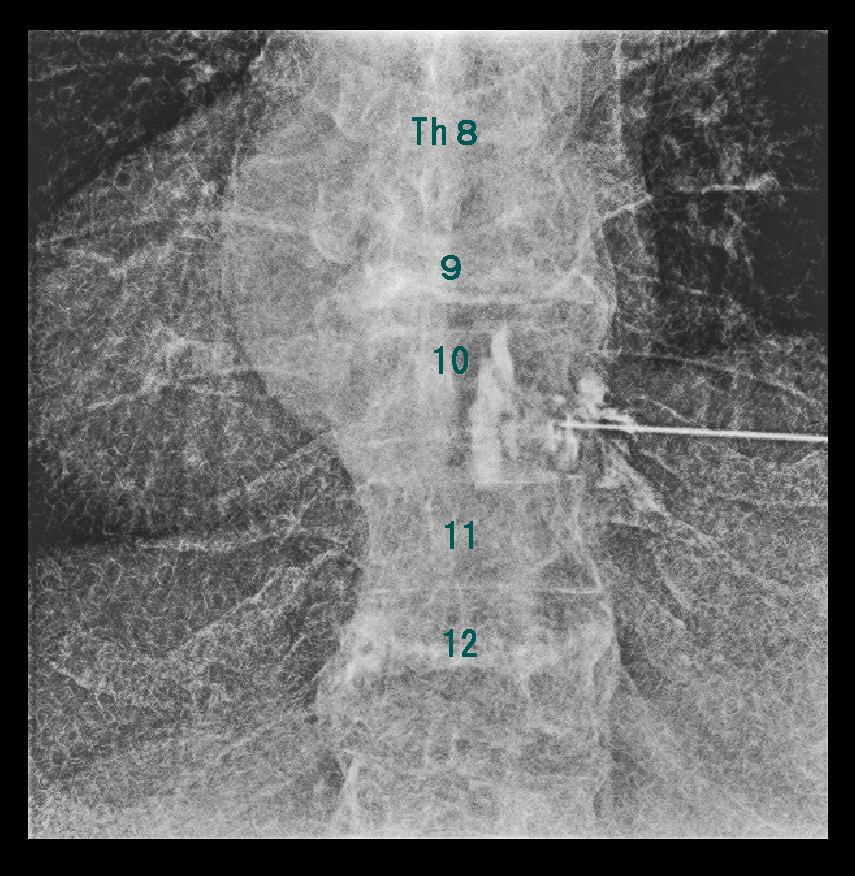

初診時RB.jpg

Th11-12高位で圧迫受けているTh12神経根ブロックを施行しました(※)。

※当時私は胸椎レベルの神経根ブロックには慣れていなかったため、実はこの患者さんのブロックでは高位を誤ってL1神経根ブロックを施行していたのですが、幸いブロックは効果を現し、腰痛は軽減しています。